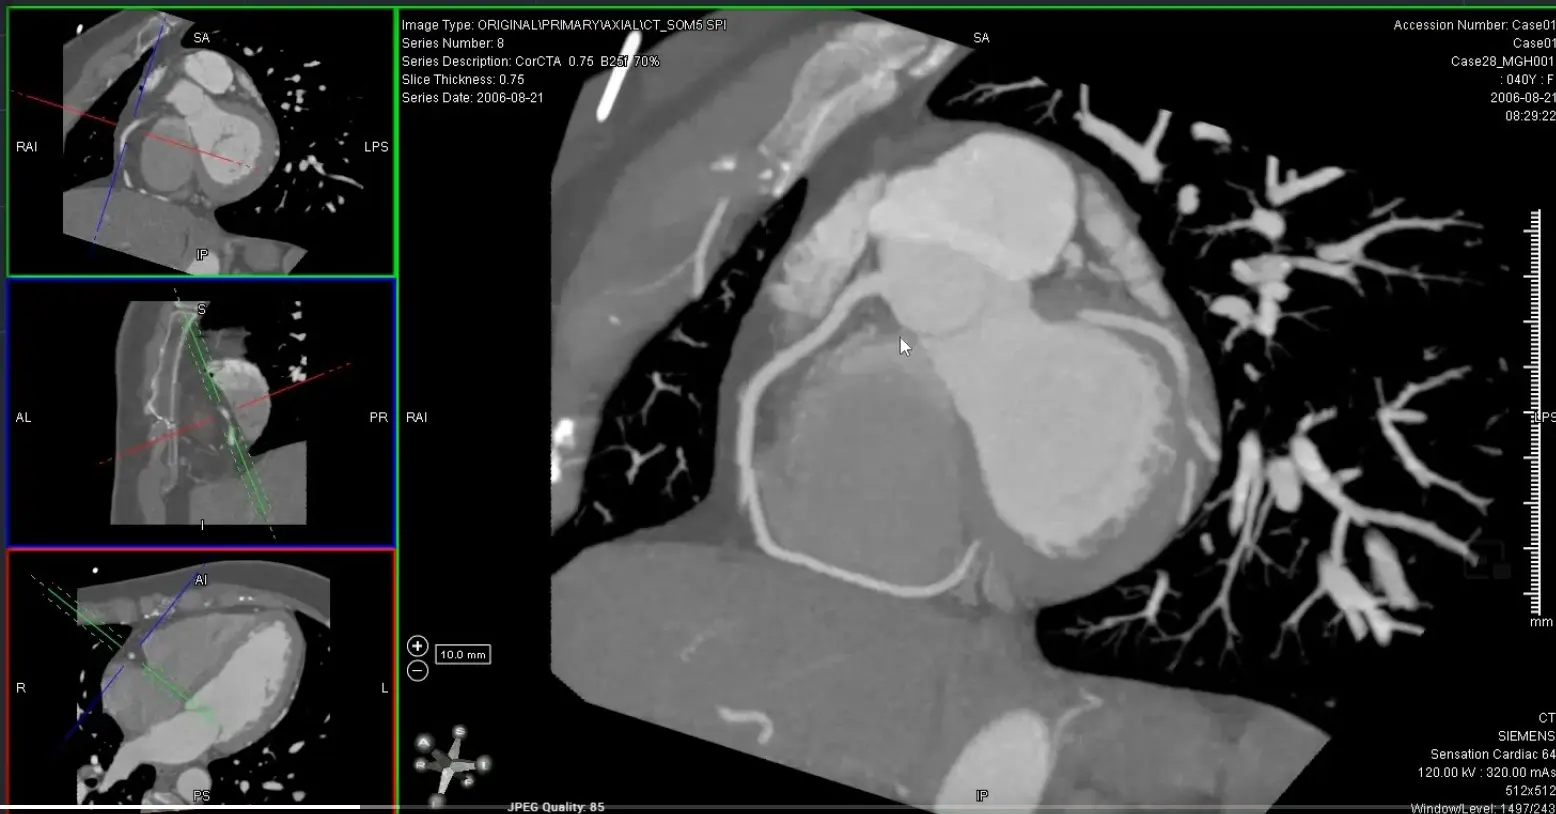

’C’ view of RCA

Useful to view RCA and LCx

Both the RCA and LCx lie along the atrioventricular groove, so the ‘C’ view is useful to evaluate the RCA and LCx. When you get your RCA lined up (as below) in the MIP projection, you can scroll along and assess the LCx as well.

- Coronal view: Position crosshair (⌖) at mid-RCA

- Axial view: center on the SAX view of the RCA

- rotate ⌖ in the axial view until you are aligned parallel to the ventricular septum on your coronal window

- In your axial view, rotate ⌖ to align the orthogonal view (e.g. coronal window) so that the orthogonal view is along the atrioventricular groove

- Switch to MIP view

- MIP will help give you an overview of the vessel. Once you identify some areas of concern → switch to thin-slice images for closer investigation 🔍 and evaluation for stenosis.

- Go down to the thinnest possible section within the MIP view

Avoid assessing diameter stenosis using thick-slab MIP

When quantifying stenosis, you will always want to use thin slice images.